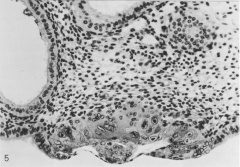

Tissues at and near implantation site